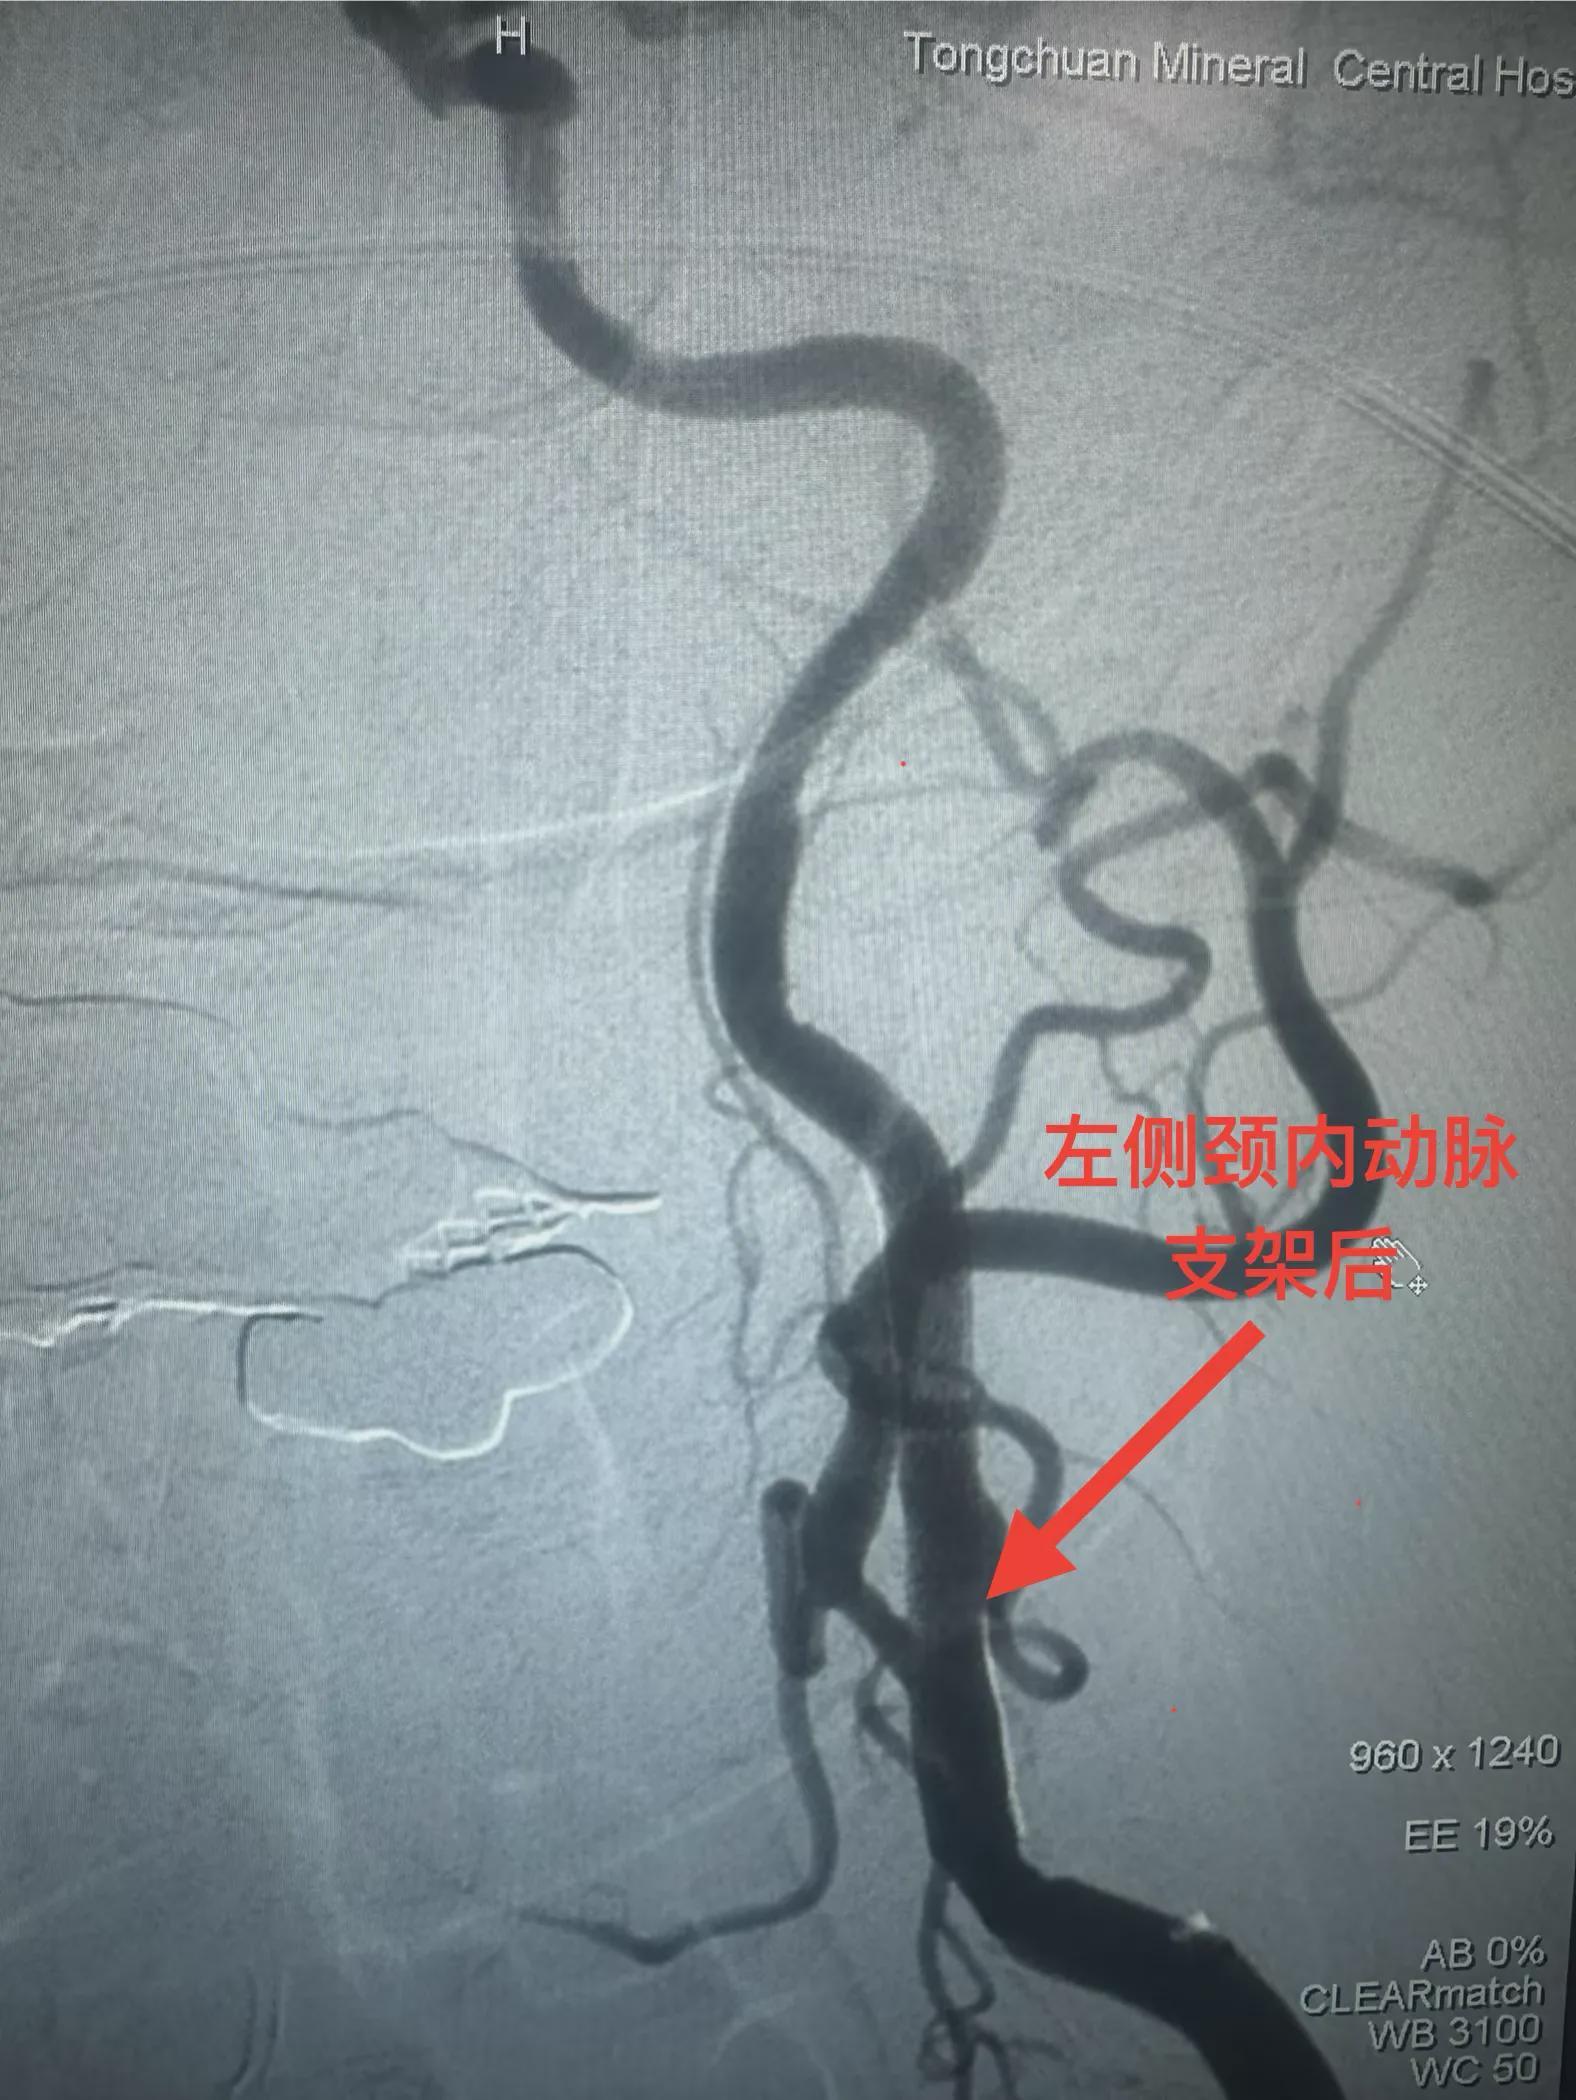

患者系77岁女性,因发作性言语不清、右侧肢体无力6小时入院。入院后,行核磁共振检查提示多发性陈旧脑梗,并进一步行全脑血管造影,显示左侧颈内动脉起始部中度狭窄。考虑到患者病情特点,铜川矿务局脑血管首席专家兼卒中中心名誉主任李健教授和学科带头人邵元主任决定带领团队采用OCT技术进行辅助支架植入治疗。

神经内二科团队为患者行球囊扩张手术后,经导引导管将超声诊断导管送至狭窄处远端,连接专用超声诊断仪器后进行了血管腔内超声扫描,清楚显示球囊扩张后血管形态,及血管内膜与斑块破损情况,并在超声诊断基础上,根据血管形态判断,准确置入支架,精准解除了血管狭窄,让患者获得了更为精确的治疗。